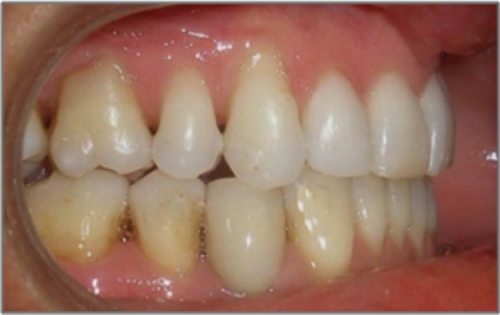

44 year old female:

Diagnosis:

- Upper and lower arch collapse due to missing teeth

- Retrusive angulation of upper & lower front teeth

- Severe collision and wear of front teeth

Treatment:

- Combination of Invisalign and braces

- Creating space for placement of an implant in the lower arch

- 28 months